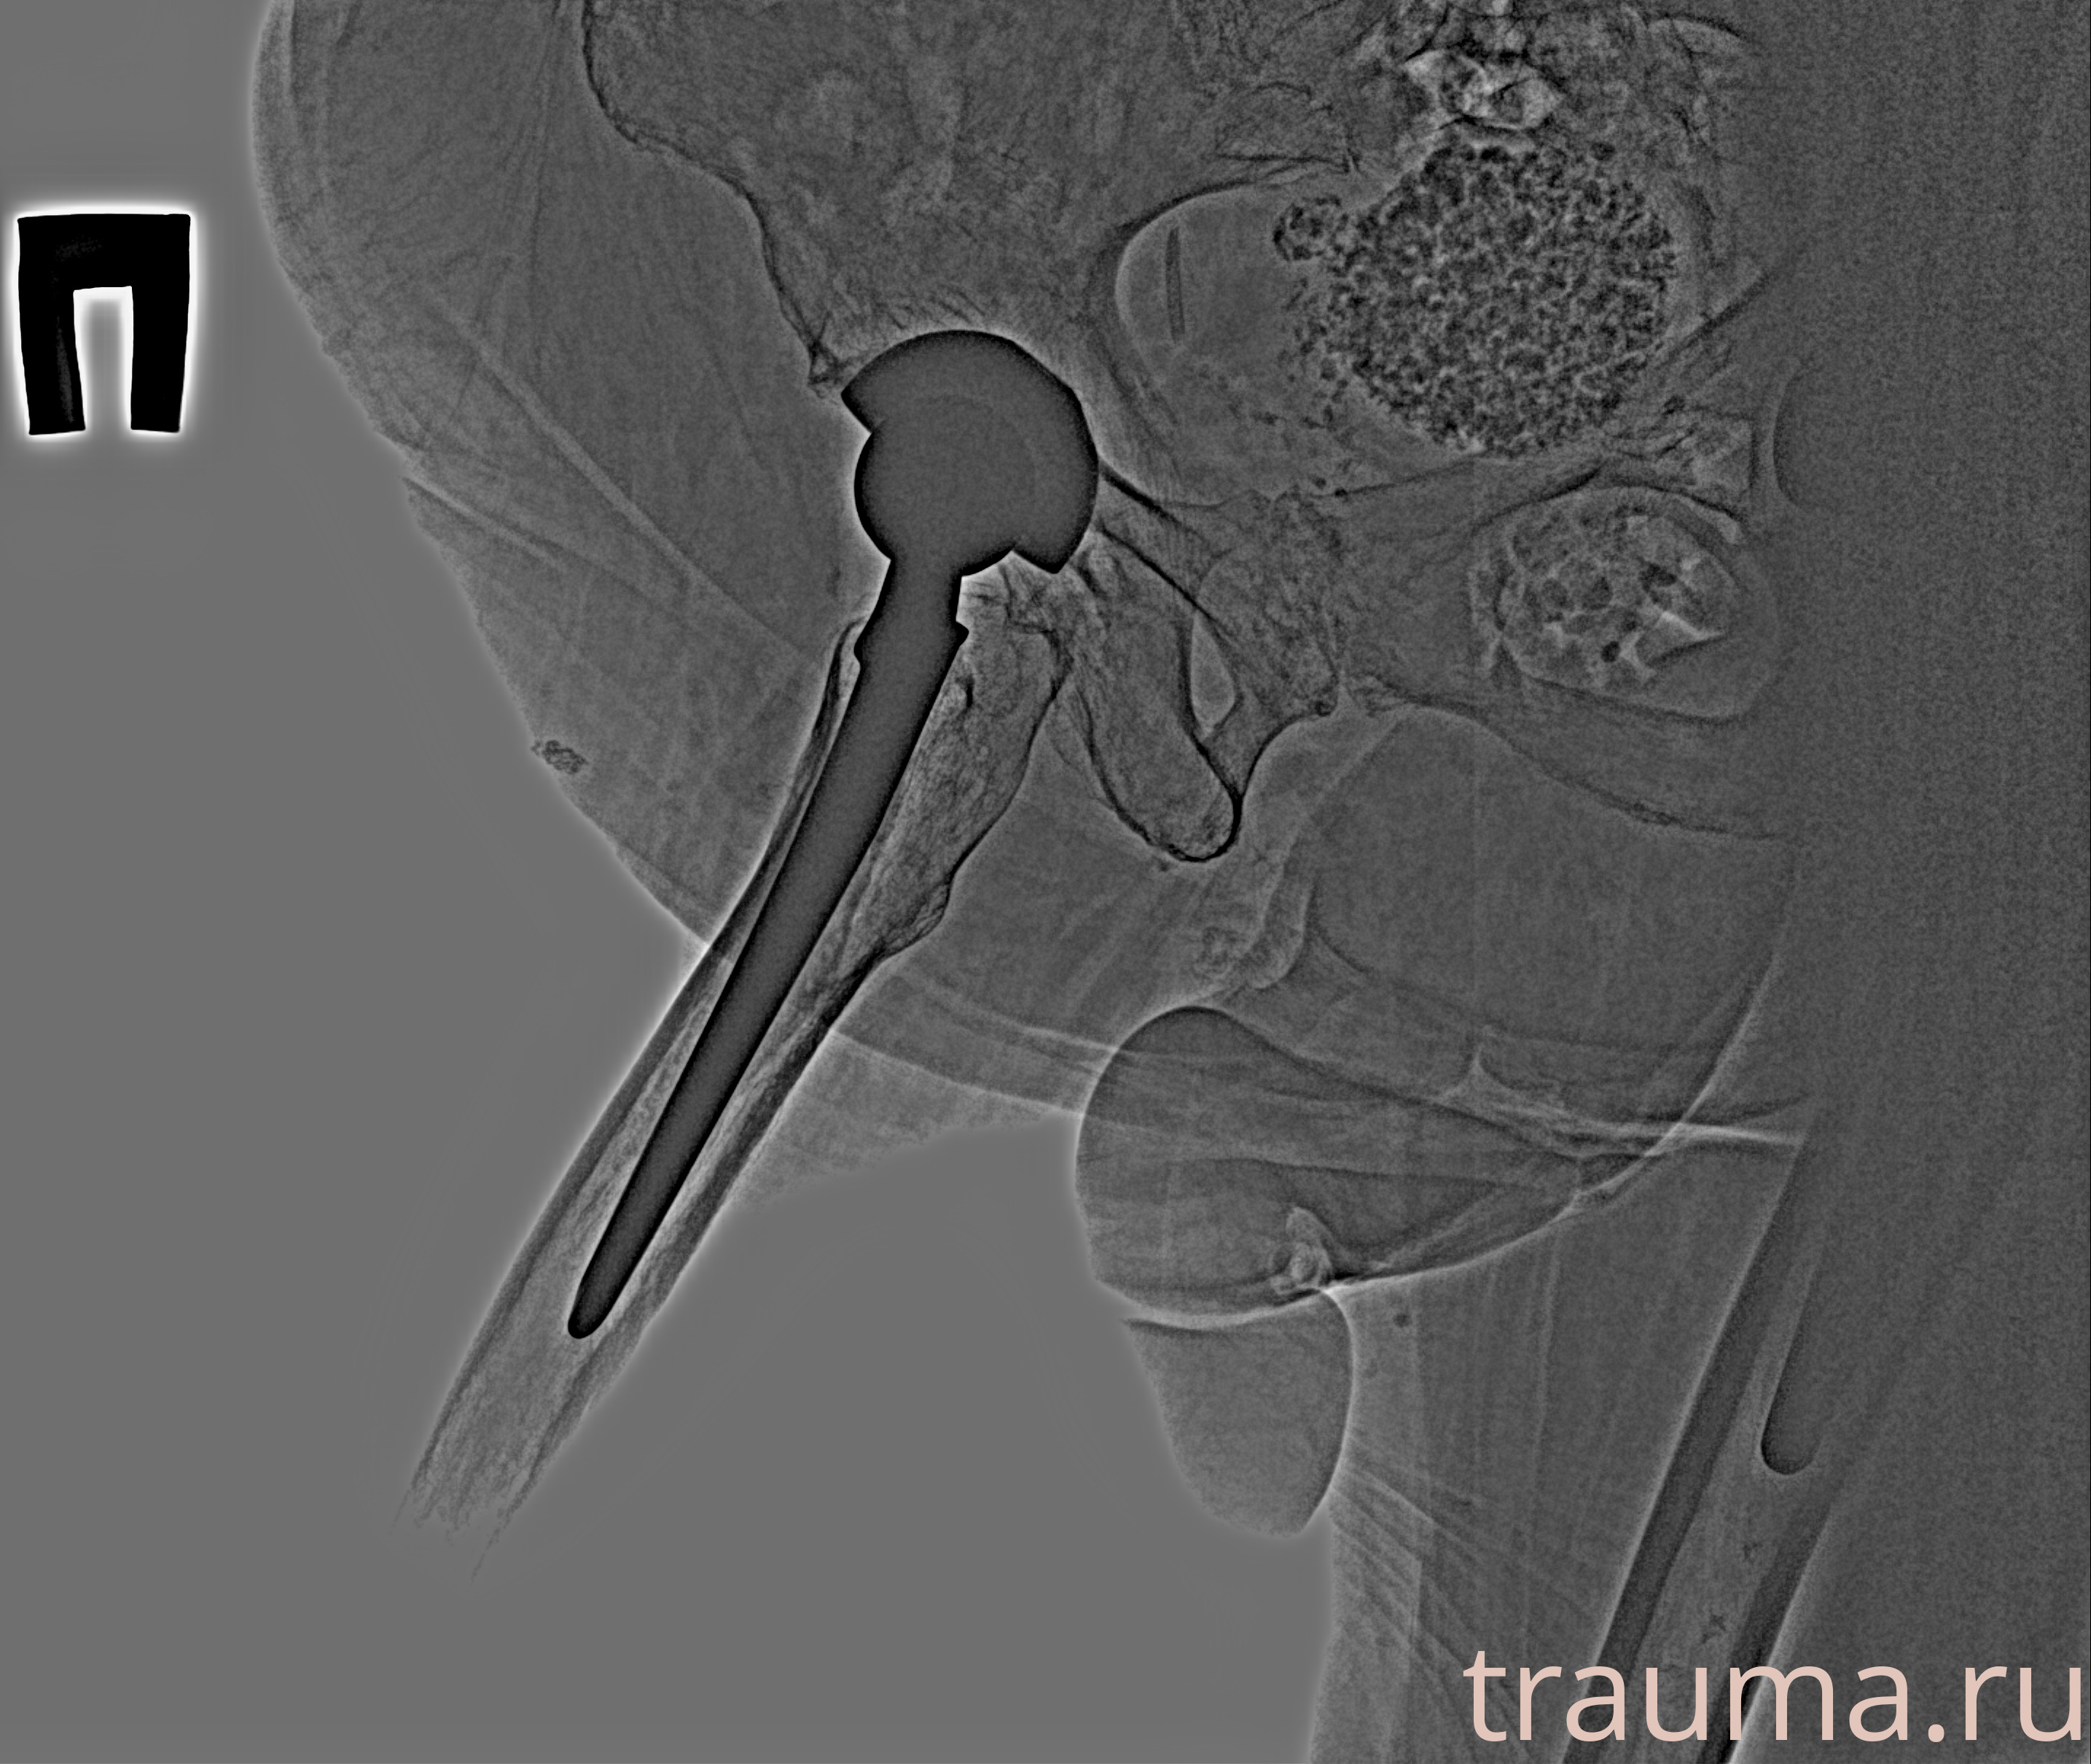

Рентген на дому: по вашему адресу приезжает врач-рентгенолог, травматолог-ортопед с мобильным рентгеновским аппаратом, проводит диагностику травмы или заболевания, делает необходимые рентгенограммы, дает рекомендации по дальнейшему лечению. Получить качественные снимки в домашних условиях возможно благодаря уникальной методике, разработанной МосРентген Центром для института  Склифосовского